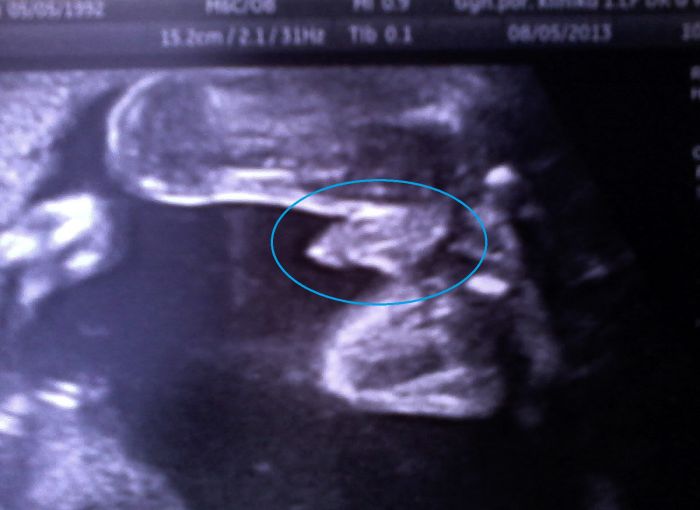

Ahoj holky,tak včera proběhla velká vizita a kotrolní UZ..Čípek je podle dr.poměrně hezký,naměřila 28mm,kdyby měla být hodně přísná a z V se pomalu uzavírá na T,tak kéž by se uplně uzavřel a držel..

Odhad váhy je 536g a prý byl malej krásně napapkanej a je to vitání,úplně zdravý miminko-po tom co předváděl spíš chlapák jako hrom..

Doteď mlžil a nechtěl ukázat,tak se oklukovi více méně spekulovalo a včera to tam roztahoval,až to mlátilo do očí..

RDr. si strašně pochvalovala super přehlednost a podrobně nám ukázala i mozek,byla z toho úplně nadšená,že je to málokdy takhle skvěle vidět a že je škoda že jsem byla na screeningu,jinak by mi ho udělala..

Docent byl taky moc hodný a říkal,že to vypadá docela dobře,ale nesmíme se ukvapit a určitě si mě tu ještě nějaký ten týden nechají,aby se vidělo co čípek a bříško..Oficiálně mi podle měření posledních pár týdnů sjednotili TP s terminem poslední ms,dokonce to přepsali i v těhu průkazce a dneska jsme 23+4tt a TP tedy vychází na 29.11,což má narozeniny můj dědeček..

Na závěr posílám pár fotek z 21tt,moc se mi líbí a gratuluji k úspěšným kontrolám..